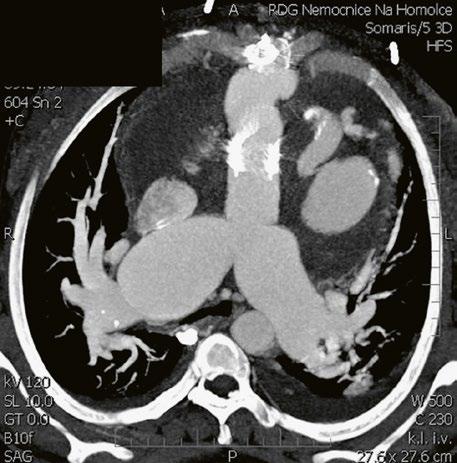

Supravalvární pulmonální stenóza a stenózy větví plicnice bývají součástí komplexních VSV (např. Fallotovy tetralogie) nebo syndromů (Williamsův syndrom, syndrom Noonanové, syndrom vrozené rubeoly, Alagillův syndrom aj.) (Obr. 45.39). Získané stenózy větví plicnice, ale i úplný uzávěr větve plicnice můžeme vidět po spojkových operacích podle BlalockaTaussigové (Obr. 45.40, Obr. 45.41). Pro zobrazení supravalvárních a periferních stenóz plicnice je optimální CT angiografie (Obr. 45.40, Obr. 45.41, Obr. 45.42, Obr. 45.43).

Obr. 45.40 CT angiografie, 8mm stenóza a deformace levé větve plicnice (šipka) po spojkové operaci podle BlalockaTaussigové v dětství LPA – levá větev plicnice, PA – kmen plicnice, RPA – pravá větev plicnice

Obr. 45.42 CT angiografie. Dilatace kmene plicnice (PA), periferní stenóza v oblasti bifurkace a odstupu pravé větve plicnice (RPA) označena šipkou, odstup levé větve plicnice (LPA) je také lehce zúžen.

Obr. 45.41 Uzávěr levé větve plicnice jako následek provedené spojky podle BlalockaTaussigové v dětství, CT angiografie

Obr. 45.43 CT angiografie, šipkou označena významná odstupová stenóza levé větve plicnice (LPA), lehčí stenóza odstupu pravé větve plicnice (RPA), kalcifikace v oblasti pulmonální chlopně

AO – aorta